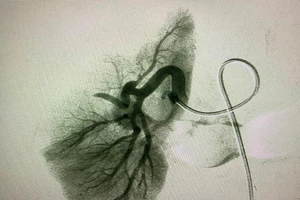

Thả 9 vòng xoắn kim loại cứu bệnh nhân ung thư vòm hầu xuất huyết nguy kịch